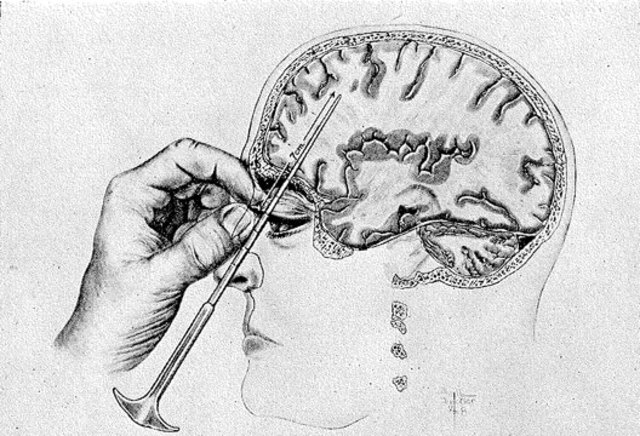

• First use of Lobotomy

First use of Lobotomy

As the study of psychology took off, António Egas Moniz performed the first lobotomy. This is where they sever connections in the brain's frontal cortex to treat some violence or mental illnesses This is no longer practiced.